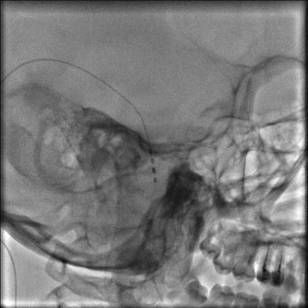

В последнее время достаточно широко используется подкожная стимуляция периферических нервов при прозопалгиях, невралгии тройничного нерва, илиоингвинальной нейропатии, тоннельных синдромах. Электрод устанавливается подкожно, пункционно в максимальной близости (в проекции) “страдающего” нерва.

Лечение илиоингвинальной нейропатии, возникшей после грыжесечения

Установка электрода при невралгии II ветви тройничного нерва